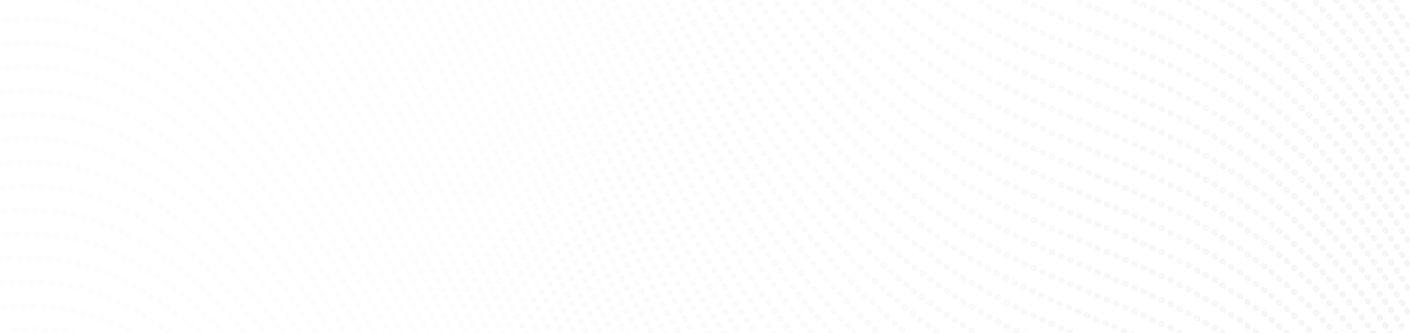

Gain practical and comprehensive updates on uveitis through the scientific symposium with expert speakers.